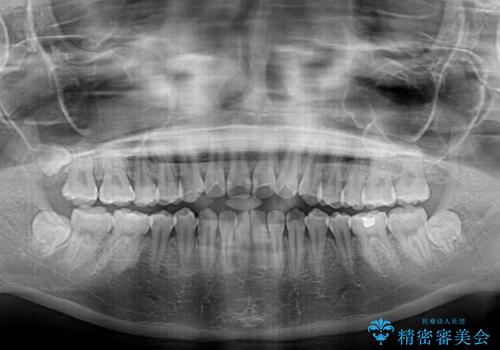

舌の突出癖による開咬と前歯の突出 インビザライン矯正治療

- 上下前歯の非接触と叢生を気にして来院された患者様です。

治療開始直後に上顎前歯に激しい痛みが発現し、矯正治療を休んだり、マウスピースの装着時間を短くしたりと工夫をしましたが、残念ながら治療途中で失活していることが分かりました。

矯正治療の途中で前歯の根管治療とオールセラミッククラウンによる補綴治療を行い、その後インビザライン1セットを用いて細かい部分を仕上げました。